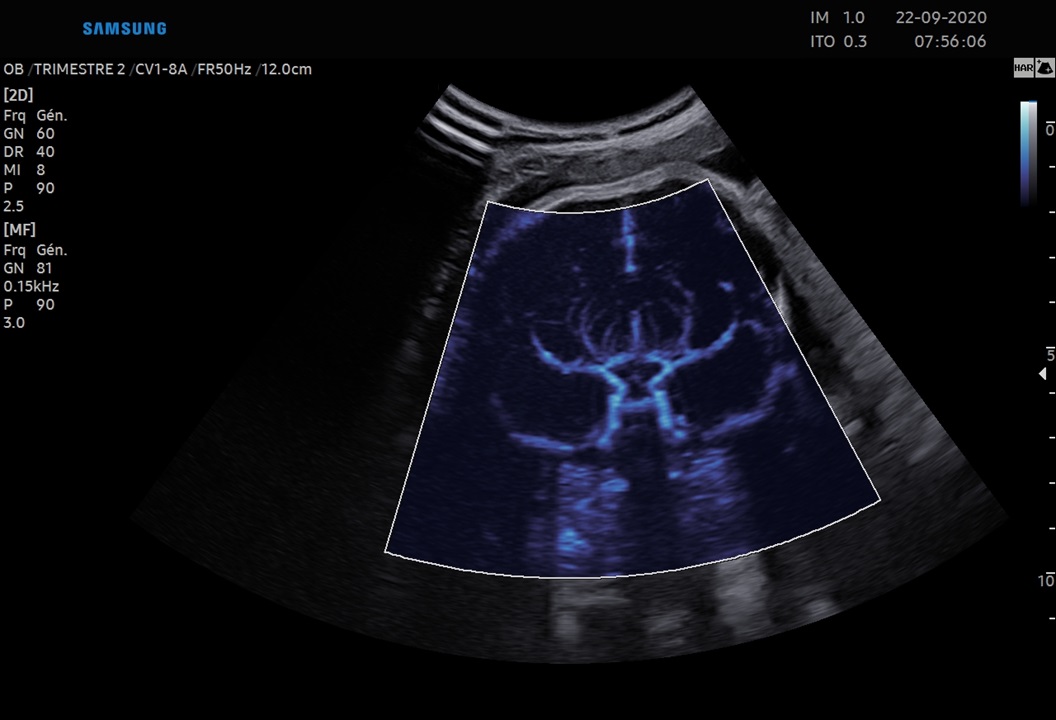

5D Heart™ est un outil intelligent permettant d’établir un diagnostic cardiaque fiable grâce à la visualisation des 9 coupes essentielles, recommandées par les sociétés internationales. Couplé à l’analyse des échanges vasculaires cardiaques, il rend l’examen du cœur plus intuitif indépendamment de la position du fœtus.